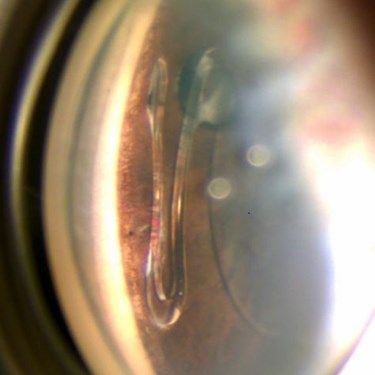

Ophthalmic Photographers’ Society (OPS) 2022 Exhibit

ASCRS and the Ophthalmic Photographers’ Society (OPS) co-sponsor a call for photo submissions of high-quality ophthalmic images demonstrating superior imaging techniques to be selected for the OPS exhibit at the ASCRS Annual Meeting. The photo selection process is highly selective and judged by ophthalmologists and OPS member photographers.

Browse the exceptional 2022 OPS Exhibit winning photos in PDF format by using the link below.